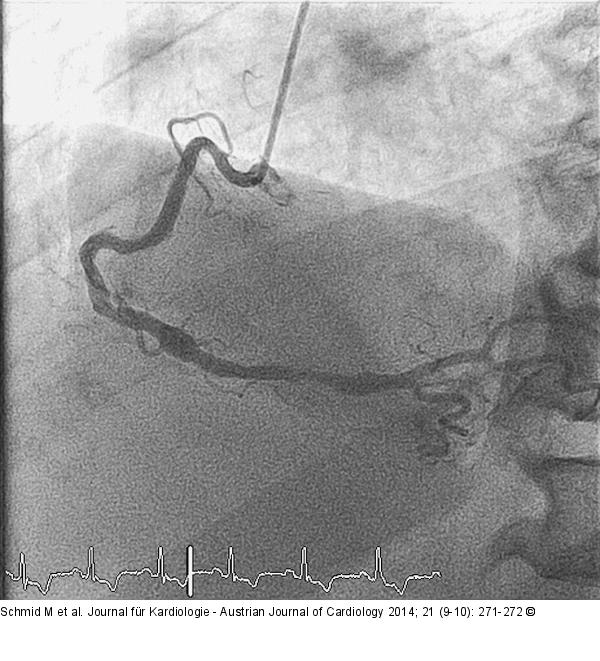

Abbildung 4: Aneurysma Kontrollangiographie nach 3 Monaten mit vollständig thrombosiertem Aneurysma. |

Kontrollangiographie nach 3 Monaten mit vollständig thrombosiertem Aneurysma. |